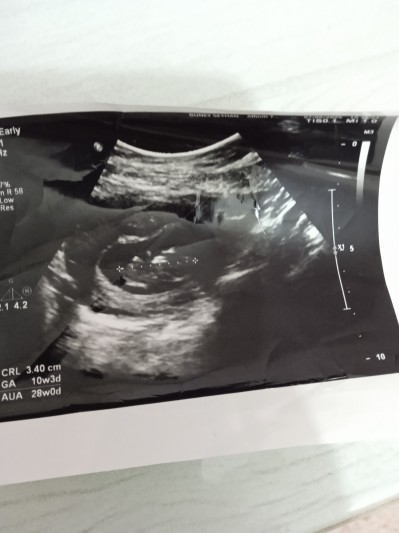

Cinsiyetini çok merak ediyorum utrasyonda anlayan varsa rica etsem bakabilirmi

Gebelik haftası 10+1

Bence kız çünkü sağda duruyo ilk kızımınki sağdaydı şimdi erkek solda duruyo

Genelde erkek sağda kız solda olur derler ama bilemedim tabi Allah neyi nasip ederse o olucak sağla solla alakası yokta işte insan meraktan her hurafeye inanır hala geliyor